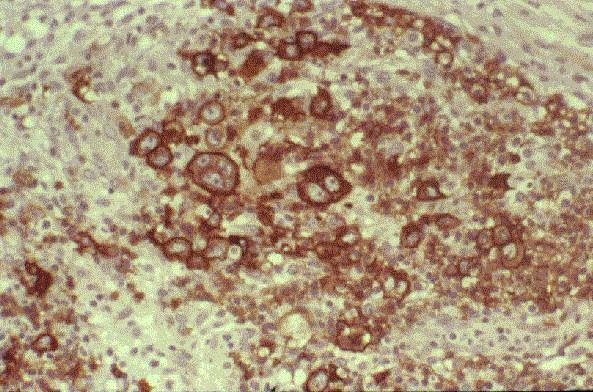

Células monomórficas, de mediano tamaño, con citoplasma basofílico amplio, núcleo redondo, nucleolos múltiples y con altísimo índice de mitosis y cariorexis y apariencia de cielo estrellado. Patrón celular cohesivo. |